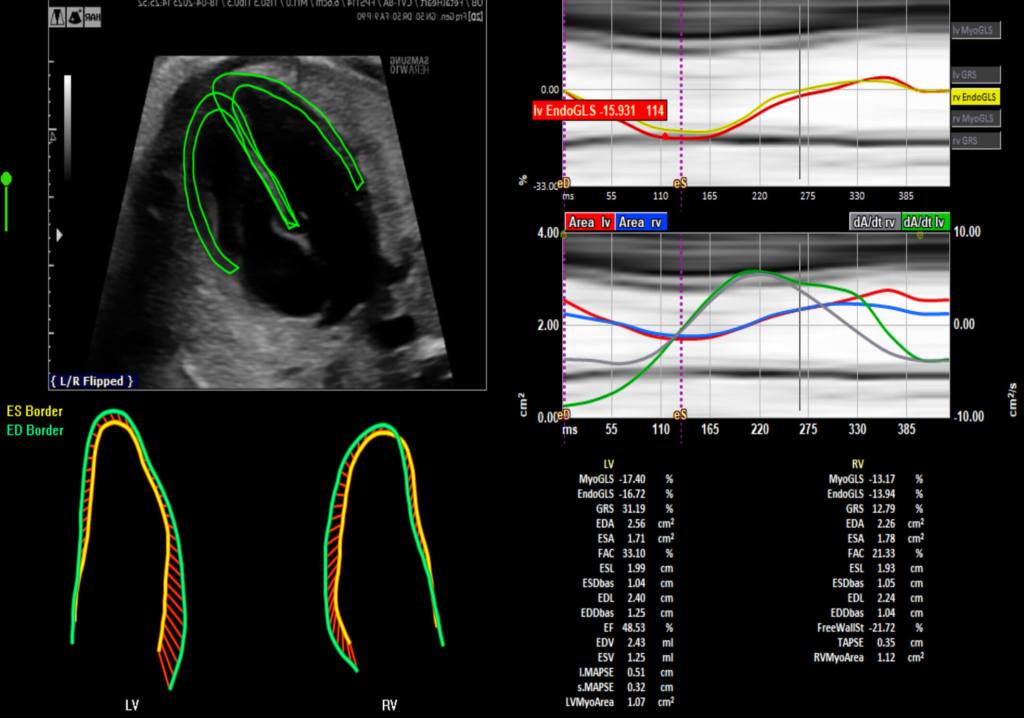

Se analizaron 208 embarazos únicos a término, sin complicaciones y en las primeras fases del trabajo de parto. A todas las mujeres se les realizó una ecografía avanzada para grabar el funcionamiento del corazón fetal con tecnología de rastreo por manchas (speckle-tracking echocardiography o STE), un sistema ya probado en cardiología pediátrica, pero poco explorado en contexto obstétrico.

El análisis se centró en detectar cómo se deforman las paredes del corazón del feto con cada latido: un indicador fino de su capacidad para mantener el flujo sanguíneo pese al estrés que implican las contracciones. En particular, se midió la deformación del ventrículo derecho, que en el útero cumple funciones clave para compensar la resistencia de la placenta y el cordón umbilical.

Los resultados de la investigación señalan que los bebés que posteriormente necesitaron una intervención urgente en el parto —ya fuera una cesárea o proceder a un parto instrumental— mostraban desde el principio del trabajo de parto una mayor deformación en el ventrículo derecho. Los propios investigadores explican que el estrés hipóxico del parto parece desencadenar una respuesta compensatoria del corazón fetal que puede observarse incluso antes de que aparezcan signos clínicos en el monitor cardíaco tradicional.